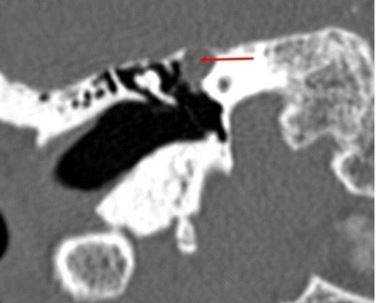

На КТ-снимке виден перелом пирамиды височной кости (указан стрелками)

Шваннома лицевого нерва: осевое КТ-изображение (костное окно) демонстрирует расширение ганглия, присутствует однородная масса мягких тканей (стрелка)

Хроническое воспаление среднего уха с холестеатомой: коронарная КТ показывает боковой свищ полукруглого канала (стрелка), вызванный эрозией кости из-за роста новообразования

Хроническое воспаление среднего уха: осевая КТ демонстрирует очаговую кальцификацию (стрелка) в барабанной полости - тимпаносклероз.